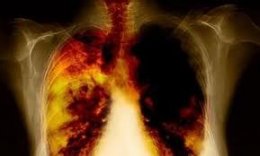

Пневмония (воспаление легких)

Пневмония (воспаление легкого) – заболевание, имеющее инфекционную природу, поражающее альвеолы. Причинами заболевания могут стать бактерии, вирусы, внутриклеточные паразиты грибки. Большая часть случаев провоцируется пневмококками, гемофильной палочкой, микоплазмами, легионеллами, хламидиями.

Симптомами являются: высокая температура, кашель, гнойная мокрота, одышка, общая постоянная слабость, боли в груди, головные боли. Читать далее